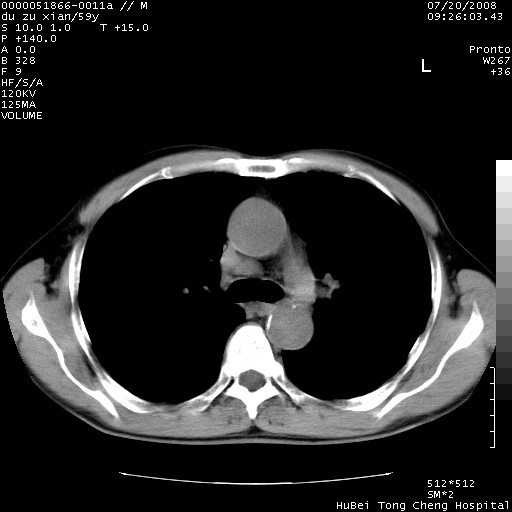

以下是引用宇宙ct在2008-8-25 23:21:00的发言:[br]右肺周围性肺癌并肋骨转移,纵隔淋巴结转移。

以下是引用zsl6918在2008-8-25 22:40:00的发言:[br]右肺周围性肺癌并肋骨转移,纵隔淋巴结转移。

以下是引用zy_zj在2008-8-26 15:24:00的发言:[br]单从病变本身,我倾向良性炎性病变,但肋骨转移了,所以说是考虑右肺周围性肺癌并肋骨、纵隔淋巴结转移可能性大。